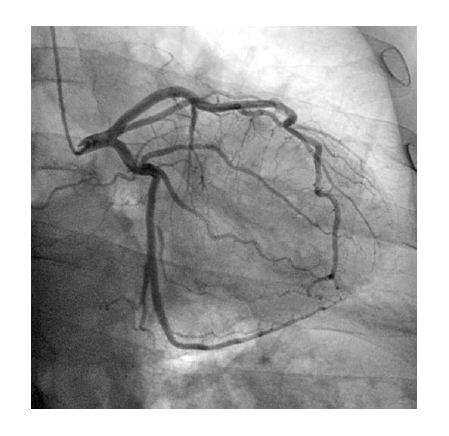

Thanks to an effective cooling system of the X-ray tube assembly, the system provides for a long period of X-ray control, which determines the use of the system for a wide range of diagnostic and medical-surgical manipulations on the heart and vessels. The subtraction angiography mode, the vascular package, the routing, and mask selection option create the necessary conditions for successful use of the system in coronary angiography, angiography, and control of electrophysiology procedures.